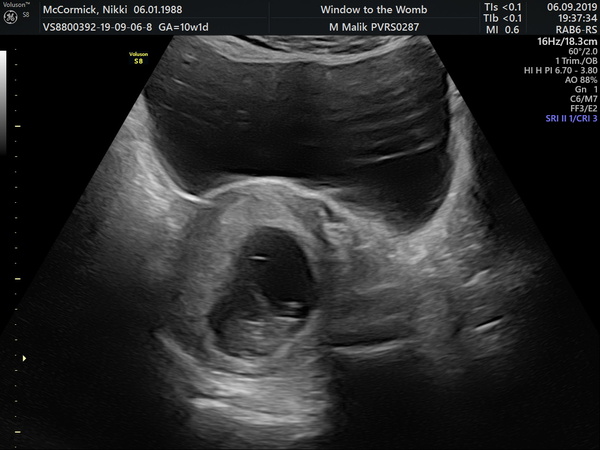

Had my scan it's so surreal. Feel much more relaxed for my holiday in 2 weeks. EDD 7th april 2020

@nikdan123 wow your scab is so clear. Was it internal or external? You’re due 3 days after me. I had external at epau last Monday due to bleeding and it was no where near as clear as that!

Scan not scab!! Blush

@Whatelsecouldibecalled yes it was internal. She tried external but wasnt very clear. Theres a pic of external one. I couldnt believe how clear it was and how much you could see for just 9 weeks 3 days. Makes it so real and exciting. Got my official first scan on 30th september. Thay was a private one for reassurance. Best £50 ever spent. Grin

@nikdan123 Wow that scan is amazing! I feel so far behind you, my booking in appointment is the day you have your 12 week scan!